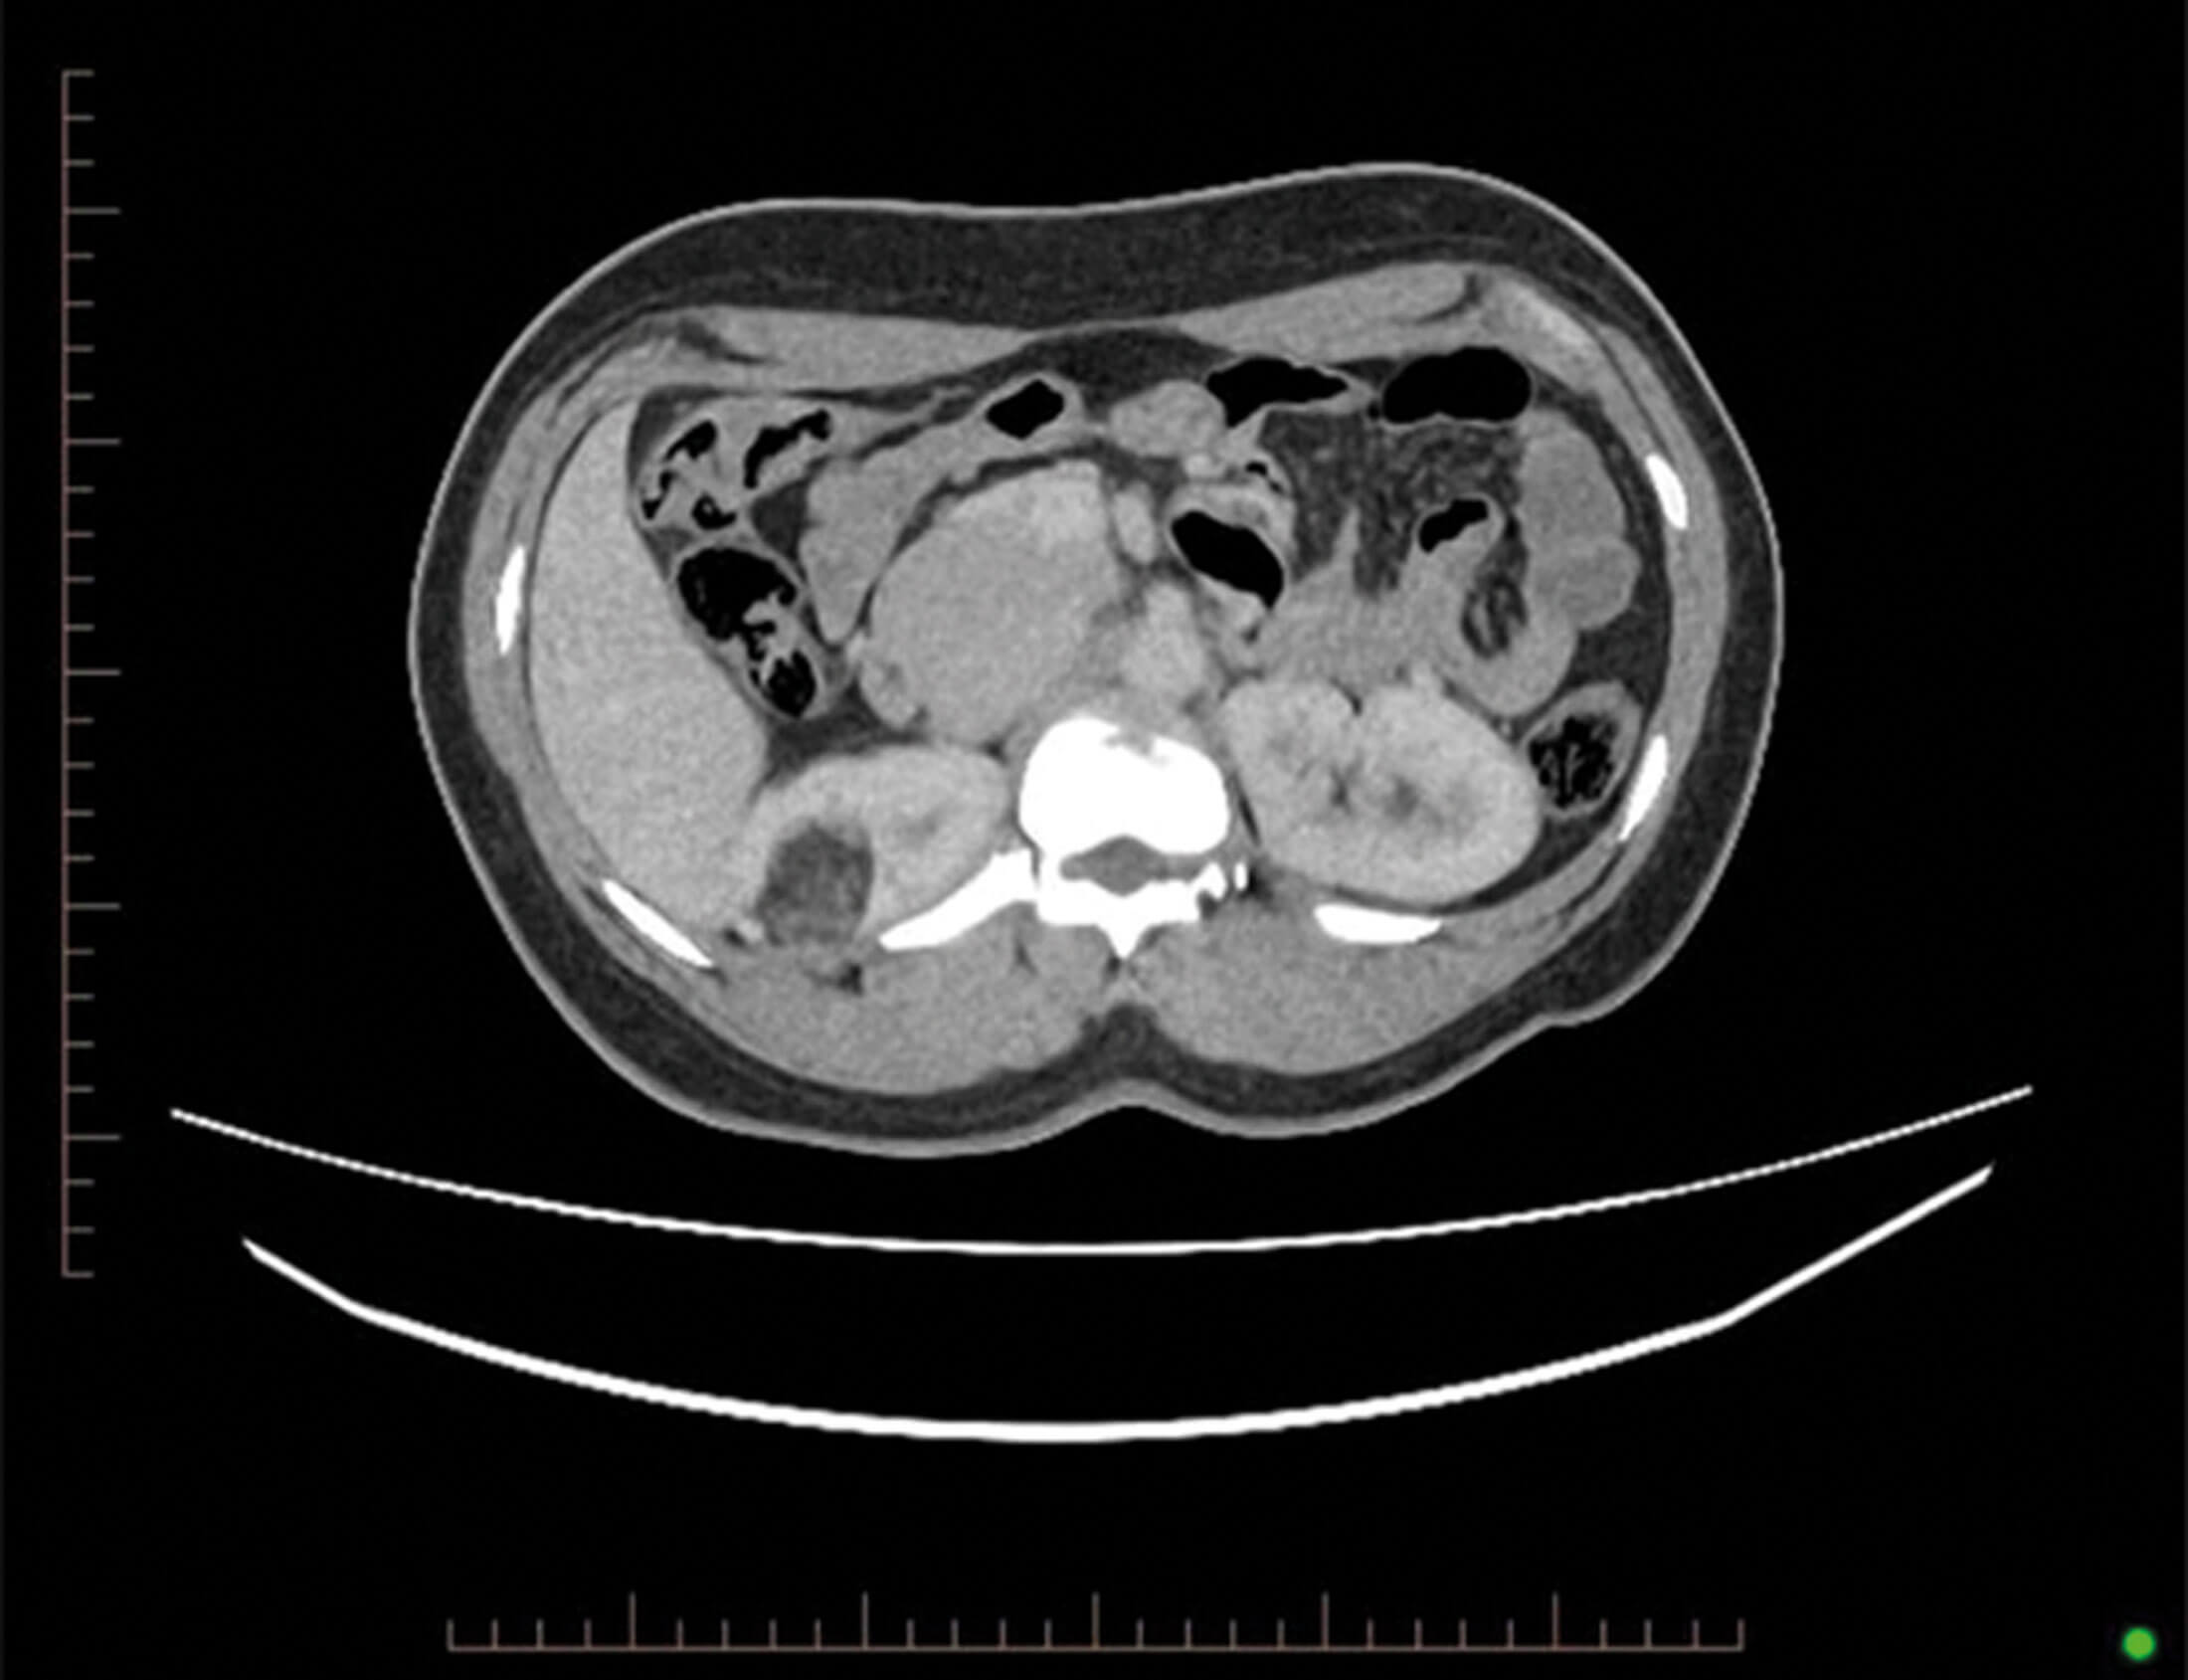

Figure 1.

- This is an axial contrast enhanced CT scan of an abdomen and pelvis. The most striking abnormality is a right-sided interpolar renal angiomyolipoma (AML), approximately 3cm in its largest dimension.